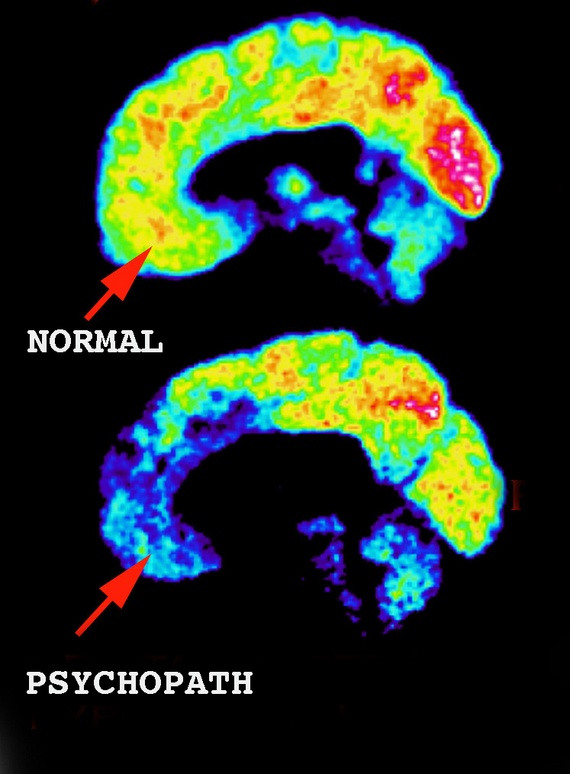

상단 :정상인의 뇌

하단: 사이코패스의 뇌. PET-CT사진.

안와전두피질(Orbitofrontal cortex) : 살인을 정당화할 때 무의식적으로 도덕적인 결정을 내리는 영역

정상인의 뇌에 비해 사이코패스의 뇌는 전두엽(이마부분 뇌)을

비롯한 전반적인 뇌부분의 활성화가 덜한 것을 볼 수 있다.